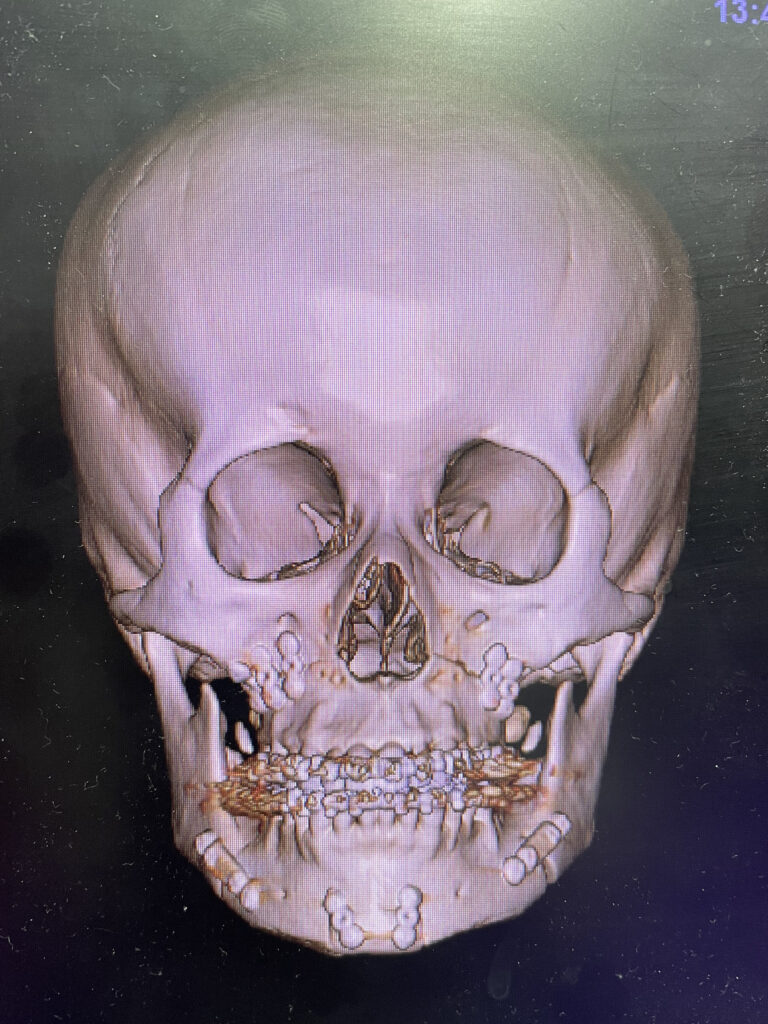

手術:上顎ルフォー1型骨切り+下顎SSRO+中抜きオトガイ形成

ほぼ予定通りの手術が行われました。